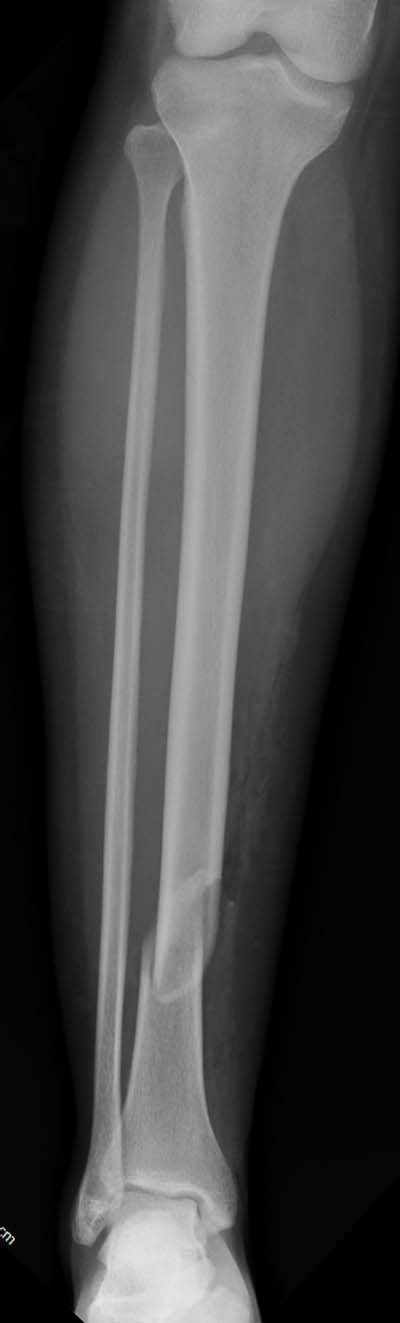

Здесь несколько снимков изолированного перелома большеберцовой с

интактной малоберцовой.  Weber clamp, блокирующие спицы и риминг в

центре канала отрепонировал перелом....